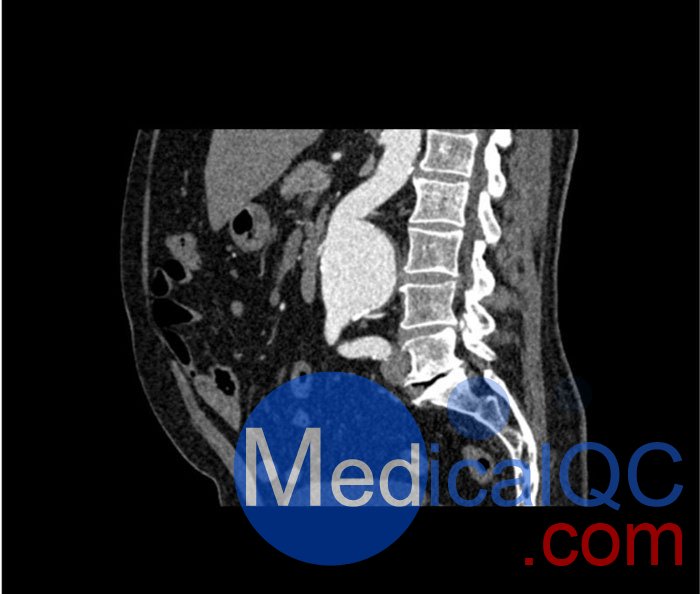

WEK53-05腹部模體,WEK53-05動脈瘤腹部模體,WEK53-05 CT血管造影模型模擬了動脈期的造影劑增強腹部。它覆蓋第一腰椎至第四骶椎。它有一個腎下腹主動脈瘤。

真實模擬脈管系統、骨骼和軟組織,包括肝臟、胰腺、脾臟、腎上腺、腎臟、胃、小腸和結腸。

肝硬化,膽囊切除術,下腔靜脈濾器,腎囊腫,腎結石,淋巴結。

SAG: